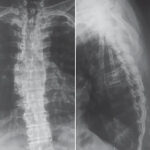

X-Ray Thoracic Lumbar (AP/LAT) View

Available services of X-ray in the Medifyhome include Thoracic-Lumbar AP/LAT X-ray View, which considers the thoracic and lumbar parts of the spine. These two views delineate the vertebra, the disc, and the surrounding structures: An anteroposterior and a lateral view of the spine. This study will help investigate any deformities, tumors, infections, or degenerating conditions of the thoracic and lumbar spine. Be it back pain, difficulty in movement, or suspicion of spinal problems, advanced imaging services offered by Medifyhome will help you out for sure.